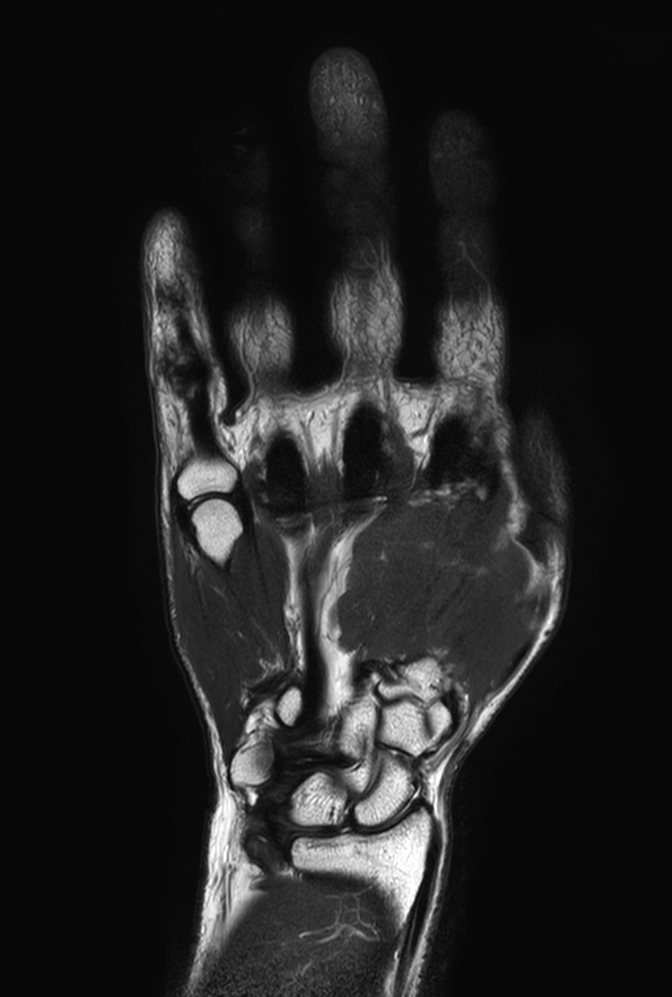

Coronal T1w TSE